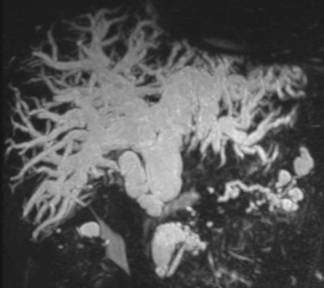

По клинической симптоматике пациенты были разделены на две группы: ,40%) – с синдромом болевой механической желтухи,,60%) – с синдромом безболевой механической желтухи. Причинами обтурационной желтухи у ,91%) пациентов явились: желчнокаменная болезнь, холедохолитиаз (Рис. 1), у,73%) – заболевания (опухолевые и неопухолевые) желчных протоков, прочие болезни панкреатобилиарной зоны, вызывающие внешнюю компрессию желчных протоков (Рис. 2), составили 30,36% (75 больных). (табл. 1).

Рис. 2 МРХПГ. Внутрипеченочная желчная гипертензия, гипертензии в протоке поджелудочной железы за счет образования головки поджелудочной железы.